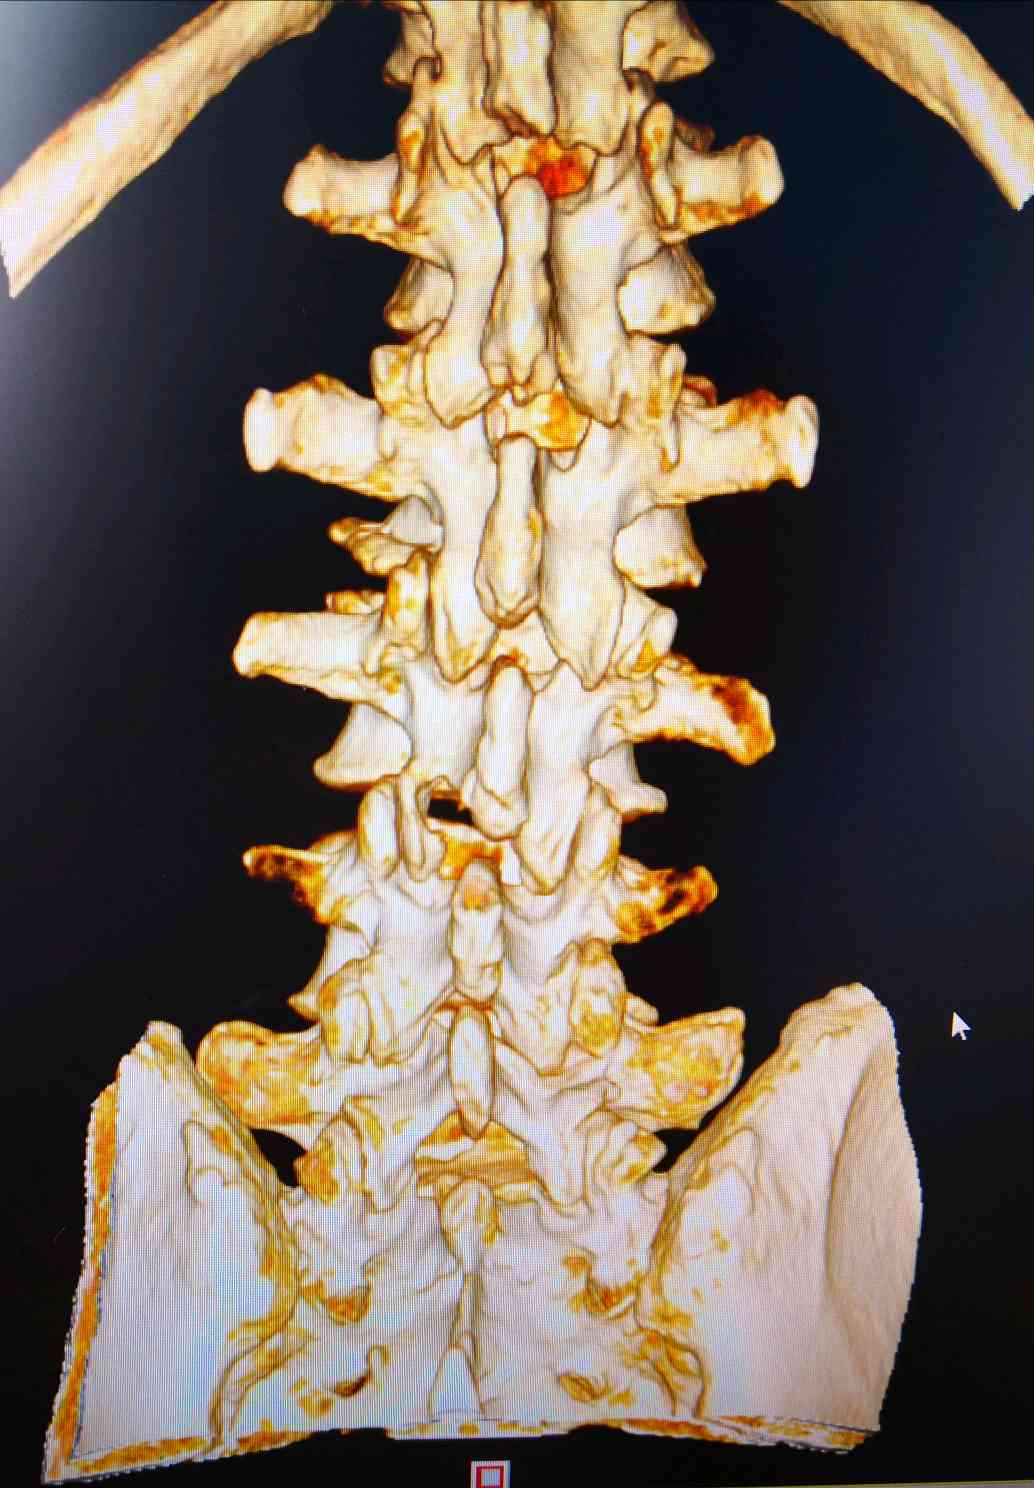

经人介绍到我科就诊,经查体,诊断为腰椎间盘突出症,如图:腰3/4椎间盘突出并重度脱垂游离,难怪疼痛那么剧烈!

其他节段也有突出,并且腰椎侧方滑脱,是钉棒内固定术还是微创内镜单纯摘除髓核?我们仔细查体发现主要矛盾还是脱出的髓核,患者也不愿意行切开内固定术,于是,采用了脊柱内镜微创手术!